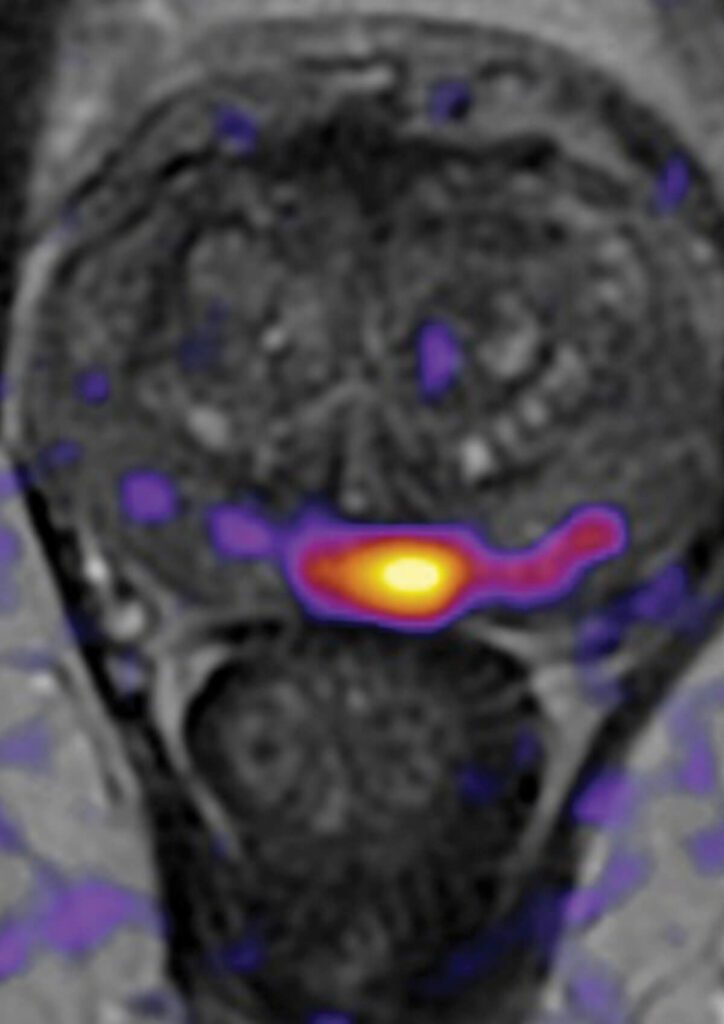

FDA-cleared advanced MRI analysis designed to enhance detection, localization, and characterization of clinically significant prostate cancer using Restriction Spectrum Imaging (RSI) and AI-assisted analysis.

- Objective assessment of brain structure volumes

- Early identification of neurodegeneration patterns

- Longitudinal tracking of disease progression

- Improved consistency and inter-reader agreement